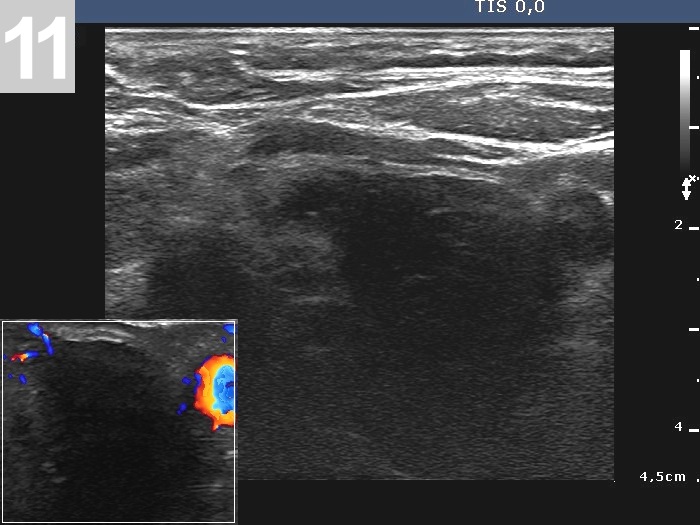

3 US of thyroid cancer

Pre- and postoperative ultrasound in thyroid cancers

Cases to be discussed on January 18, 2024